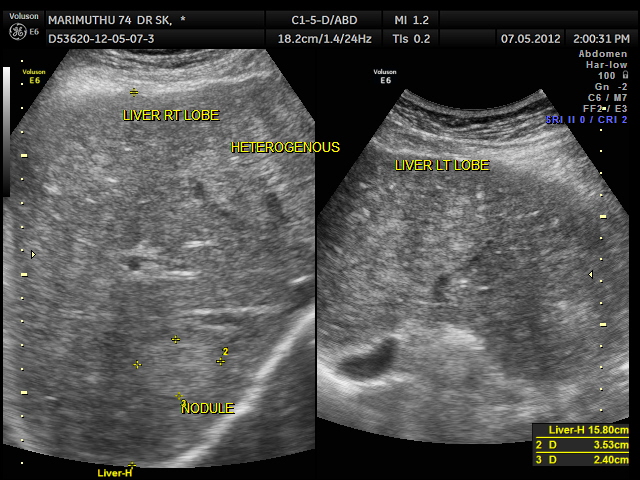

This 74 year old gentleman has been coming to me for more than 10 years for mild systemic hypertension and hypothyroidism.He used to smoke cigars until a few years ago. 3 years ago he developed unexplained giddiness and on evaluation was found to have pituitary macroadenoma. Endocrine and neuro surgical consulatations were sought and he was on cabergoline and was doing very well. In April 2012 , he came for a routine review and was asked to continue his existing medications . One week later he came again with severe right upper quadrant pain and aversion to food. There was no history of cough in the recent past. He was advised an ultrasound scan of the abdomen and the findings are as below.

Extensive FDG avid hepatic metastases involving both lobes.